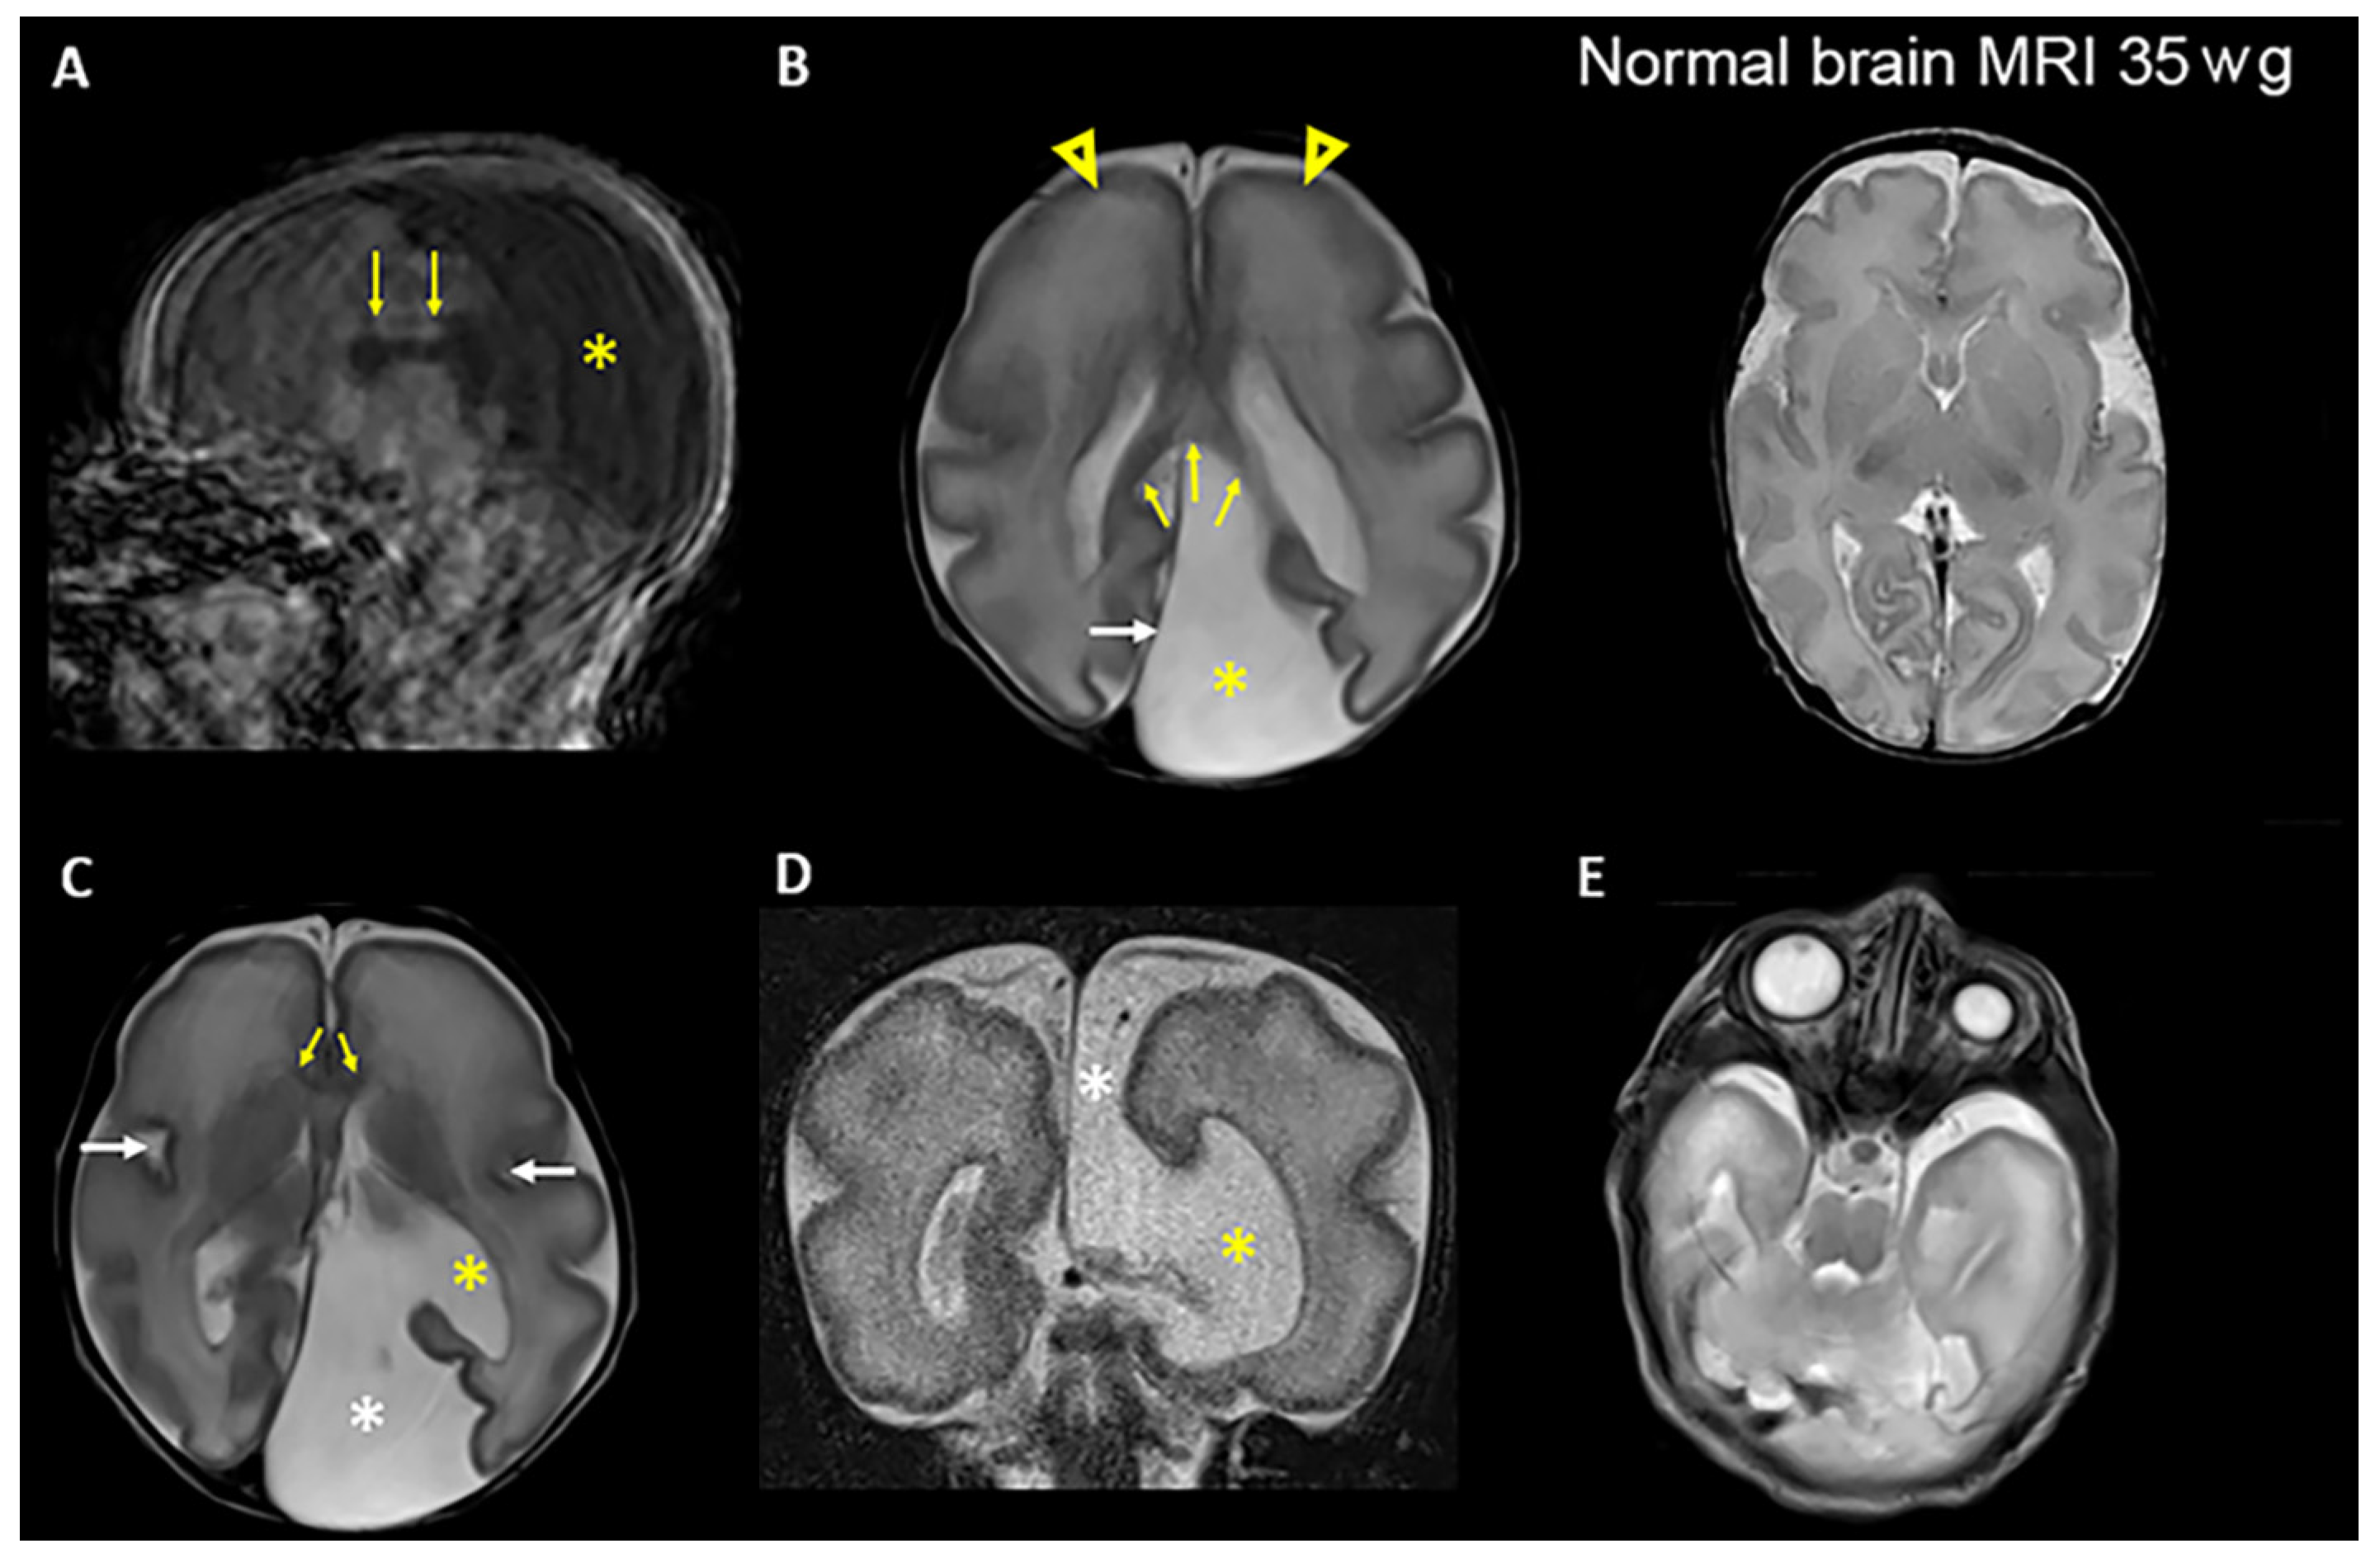

Patient 1 was a female only child, born at 34 + 3 weeks to a healthy consanguineous Lithuanian couple (Figure 1A). She was small for gestational age with weight 1360 g (<3rd centile), length 39 cm (3rd centile) and OFC 25.8 cm (3 cm < 3rd centile). Fetal ultrasound examination showed cerebral ventriculomegaly, corpus callosum agenesis, renal anomaly, duodenal atresia, and polyhydramnios. At birth, the patient needed respiratory support, and continuous positive airway pressure (CPAP) therapy was provided. Abdominal surgery was performed at day 1 due to suspicion of duodenal atresia, and an apple-peel anomaly was confirmed. After birth, bilateral renal hypoplasia was ascertained. She had bilateral microphthalmia (Figure 2) and sclerocornea. Brain MRI showed a cystic expansion of the cerebrospinal fluid (CSF). The CSF expansion was also in part secondary to reduced volume of the posterior part of the left cerebral hemisphere, chiefly due to marked hypoplasia of the left occipital lobe (compatible with colpocephaly), seemingly communicating with the left lateral ventricle (Figure 2). The cortex showed modest gyration compared to gestational age, which gave the impression of lissencephaly, and an underdeveloped corpus callosum (Figure 2). She died 26 days after birth.

Figure 2. Brain MRI images of patient 1 in the postnatal period at approximately 35 weeks gestational age demonstrate multiple congenital anomalies. (A) Sagittal T1-weighted image shows the presence of the corpus callosum, which is not properly developed (arrows). The posterior portion (the splenuim) is located further anterior than normal. CSF fills most of the posterior supratentorial compartment (asterisk). Note motion artifacts in the basal regions of the brain. (B) Left: Axial T2-weighted image shows an expansion of the left supratentorial cranial cavity (interhemispheric cyst) filled with CSF (asterisk) in the parietooccipital region of the left hemisphere. The posterior falx cerebri (white arrow) is shifted toward the right hemisphere. The splenium of the corpus callosum is visible (yellow arrows). There is primitive gyrosulcal patterning, more prominent in the frontal lobes (arrowheads), consistent with 28–29 weeks of gestation. Right: Axial T2-weighted image shows normal gyrus and sulcus formation at 35 weeks of gestation (wg). (C) Axial T2-weighted image shows the interhemispheric cyst (white asterisk) communicating with the enlarged left lateral ventricle (yellow asterisk). The genu of the corpus callosum is visible (yellow arrows). The sylvian fissures (white arrows) appear underdeveloped in both hemispheres. (D) Coronal T2- weighted image shows the communication of the CSF space (interhemispheric cyst) (white asterisk) with the lateral ventricle (yellow asterisk) on the left side through a broad parenchymal defect in the medial temporoparietal region. (E) Axial T2-weighted image shows pronounced left microphthalmia, without detectable lens.